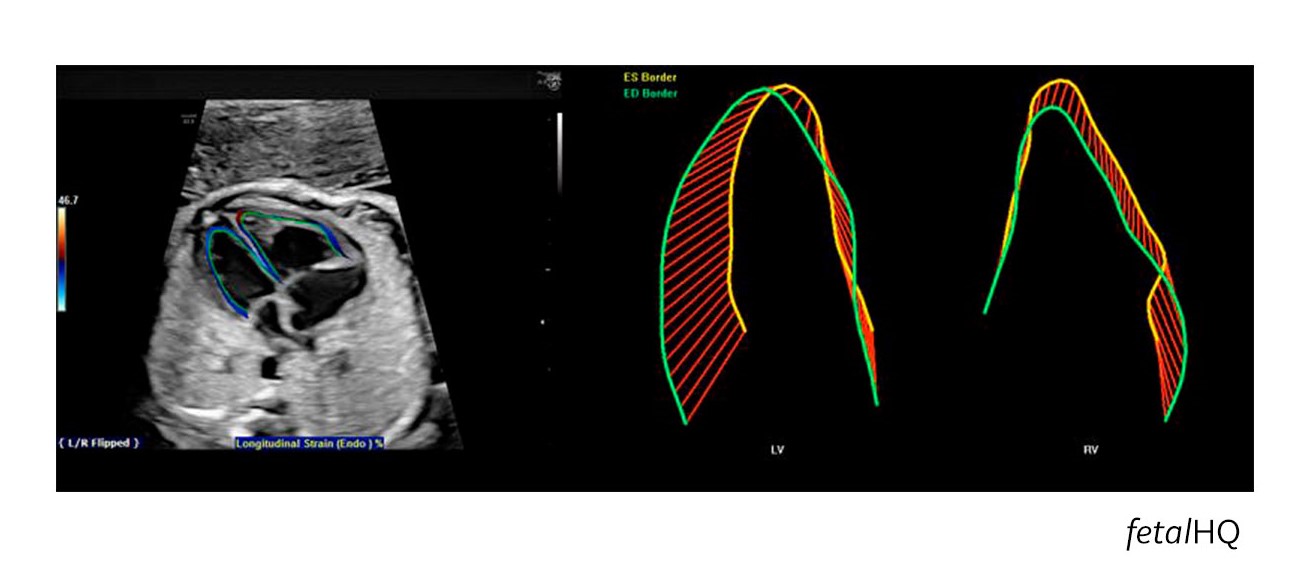

Mientras que esta velocidad es impresionante, no es lo más notable del fetalHQ,, la última tecnología de ultrasonido de GE Healthcare. Esta función en los sistemas de Voluson™ E10 miden el corazón en formas que nunca se han hecho. Los médicos ahora pueden determinar el tamaño, la forma y la contractilidad del corazón a partir de las vistas de 4 cámaras basadas en imágenes 2D y Speckle Tracking.

El Dr. DeVore tuvo la idea y adaptó el software existente de corazones pediátricos y adultos para crear la tecnología avanzada del corazón fetal. Él publicó 13 artículos revisados por pares con datos clínicos que sirven de base para el fetalHQ.2-15 DeVore sabía que, con más información sobre el funcionamiento del corazón fetal, los doctores podrían identificar anomalías y posiblemente adelantarse a condiciones prenatales potencialmente mortales como la restricción del crecimiento intrauterino. También ve el gran potencial para comprender y tratar el síndrome de transfusión de gemelo a gemelo.